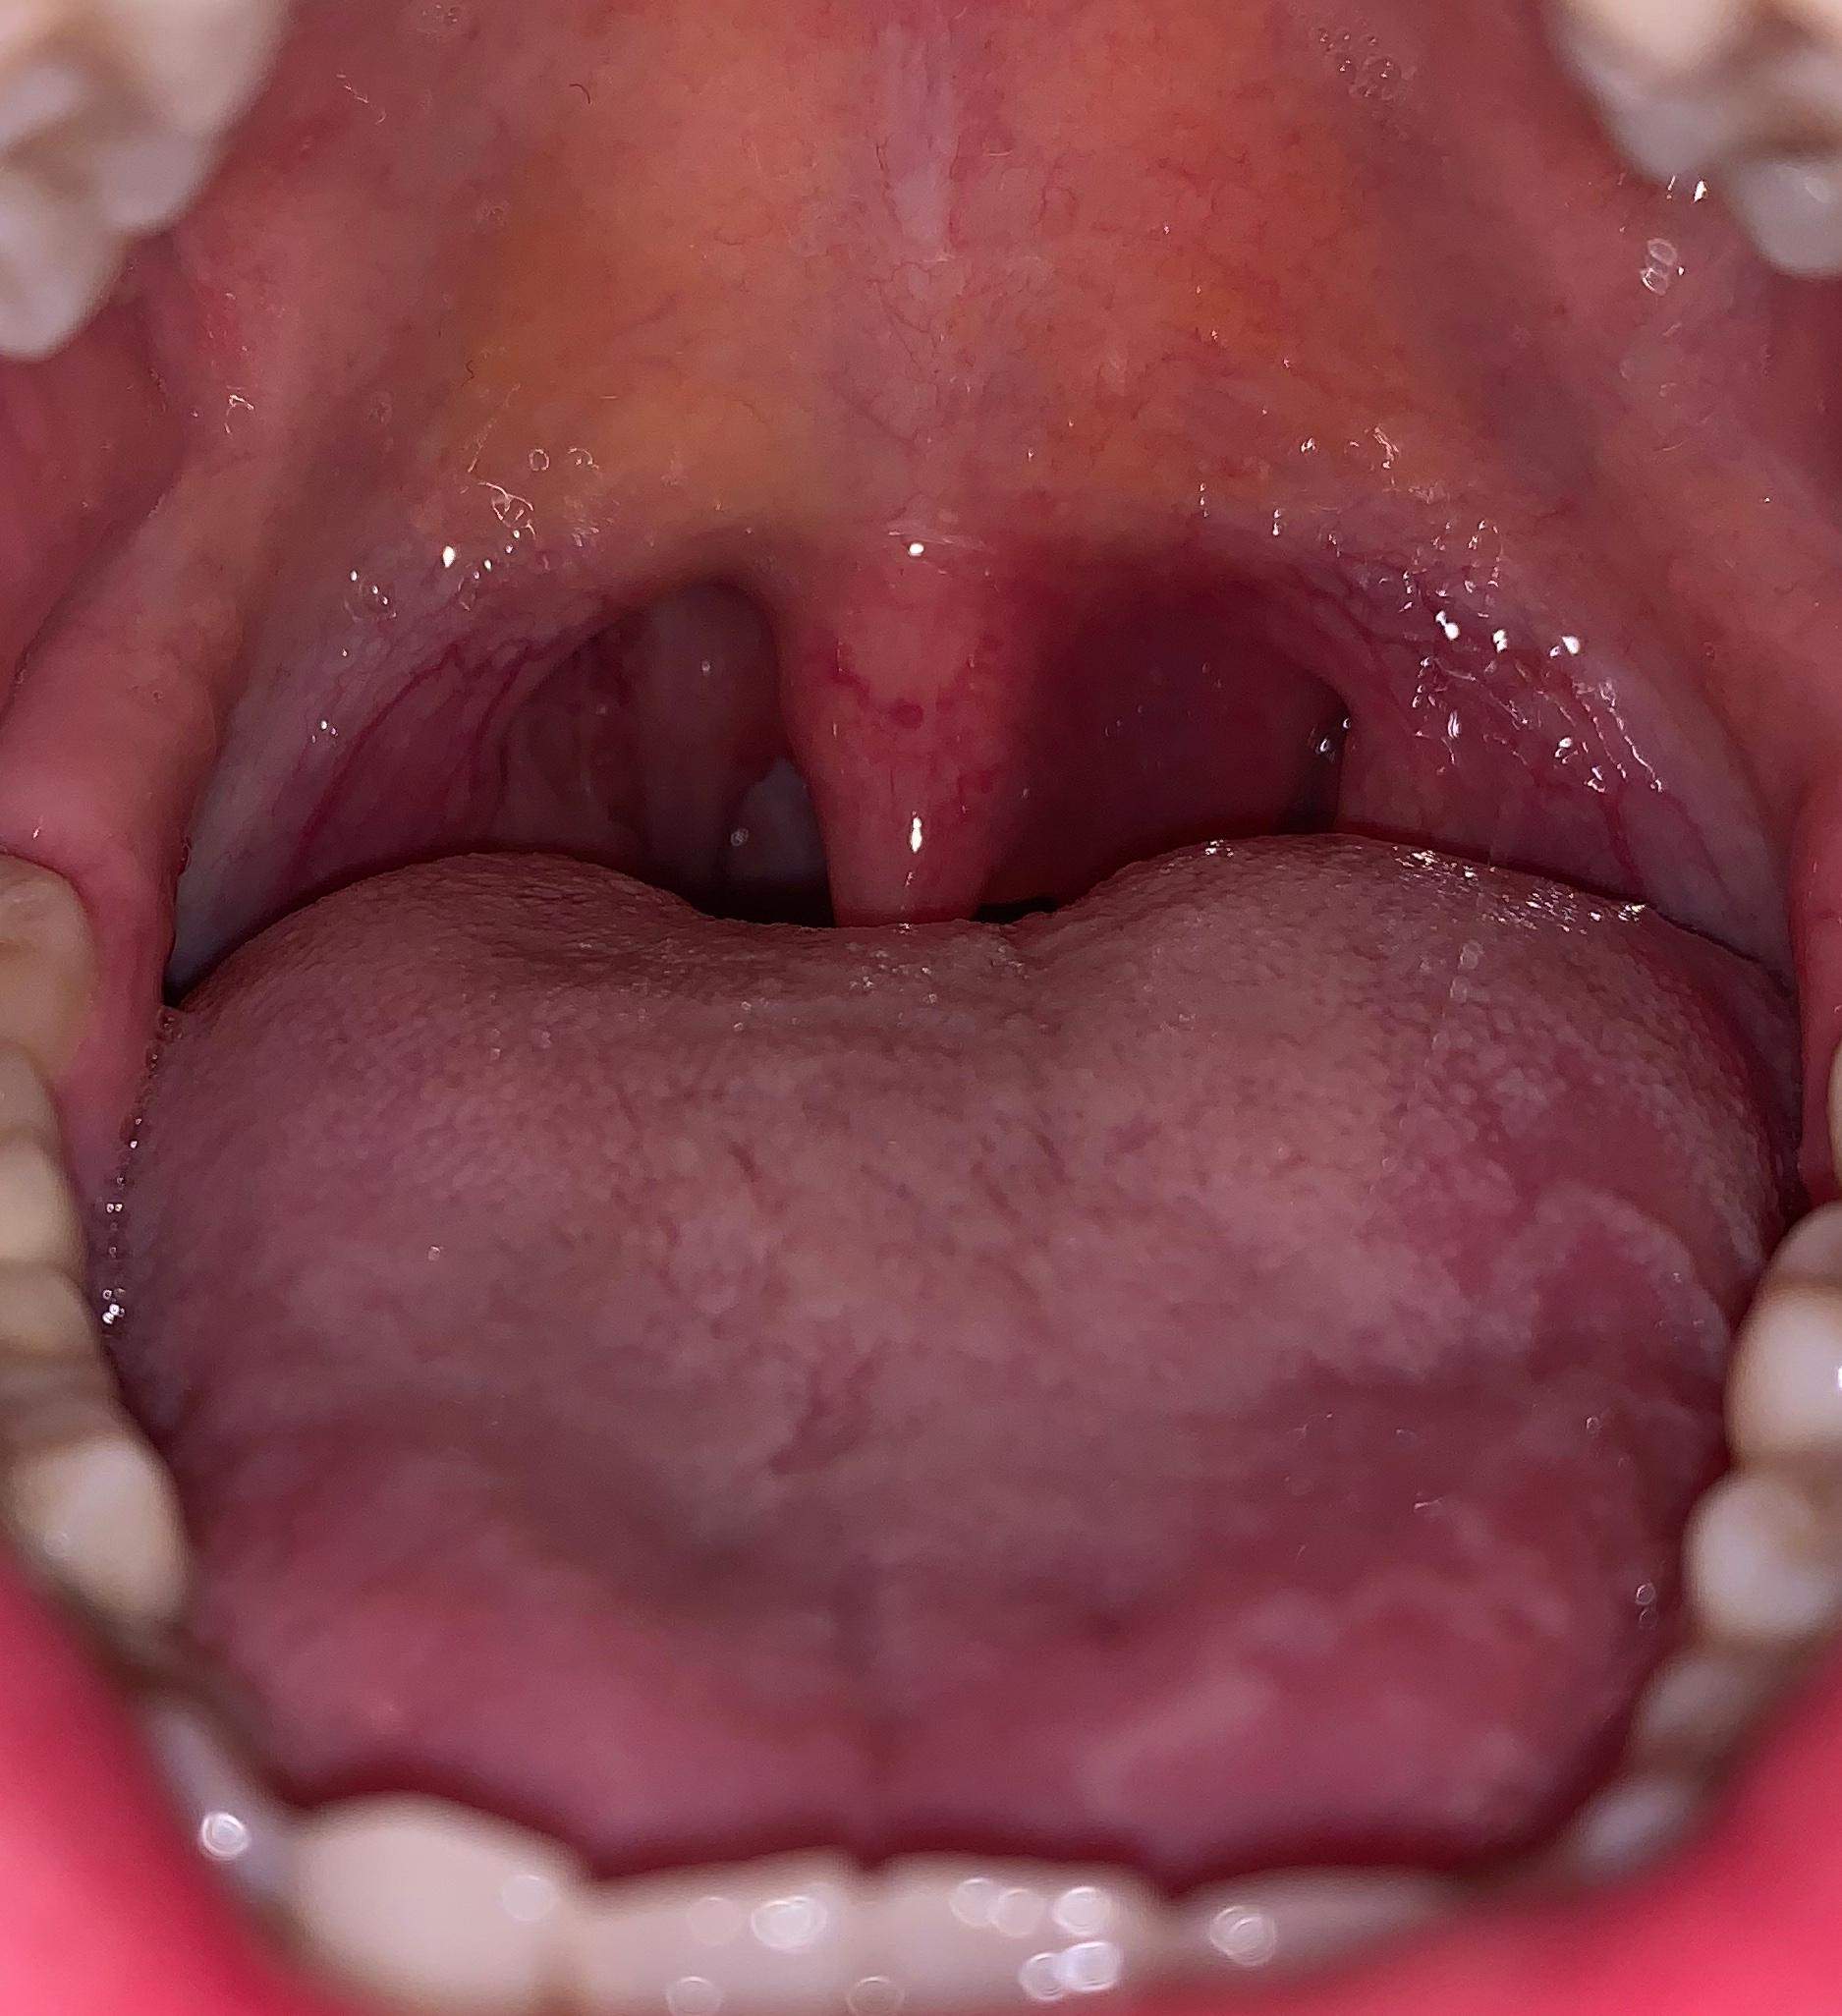

Eine Schwellung des Zahnfleisches ist ein Anzeichen für eine Entzündung. Hierbei wird Flüssigkeit im Gewebe eingelagert, welches durch eine Allergie oder Infektion hervorgerufen werden kann. Weitere Auslöser können sein: ein traumatischer Zahnunfall oder eine Verletzung. Ödeme. Blutungen. Fisteln am Zahnfleisch.. Auch eine Schwellung der betroffenen Areale (z. B. am Zahnfleisch, Gaumensegel, Gaumenzäpfchen, den Gaumenmandeln oder dem allgemeinen Oberkiefer) ist ein klassisches Entzündungszeichen. Begleitende Bläschen können auf einen Virenbefall oder Aphthen hindeuten. Gelbweiße Eiterherde weisen normalerweise auf eine Bakterienbesiedlung hin.

Mandelentzündung So entsteht eine Tonsillitis

Inwiefern kann eine Mandelentzündung Mundgeruch hervorrufen?

Wieder eine Mandelentzündung? (Schmerzen, Krankheit, Mandeln)